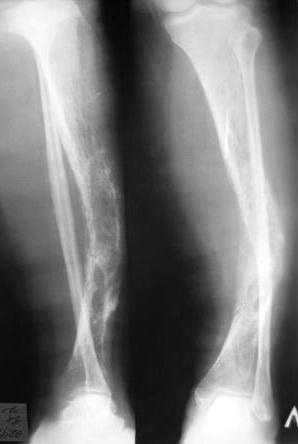

Фиброзная дисплазия?

Пациентка Ч. дата рождения 28.02.1962. Болеет на протяжении 3 лет, появились боли в левой голени, отеки голени, стопы. Обследования не проходила, лечения не получала.

Заключение гистолога: присланы скудные биоптаты из опухоли левой б/берцовой кости в виде мелких фрагментов размерами 0.2 х 0.5 см, с наличием костных фрагментов губчатого вида и мягкотканных кусочков. При исследовании: иррегулярные костные балки обычной архитектоники без атипии остеоида, лежат изолированно друг от друга, между ними зрелая клеточно-волокнистая фиброзная ткань. В прилежащей клетчатке очаги отложения солей кальция, мелкоочаговые кровоизлияния. Более всего можно думать о фиброзной дисплазии.

У нас обследование: гаммасцинтиграфия – очаги скопления препарата в левой б/берцовой кости, 8 ребре слева. Данных за б-нь Педжета нет.

Рентгенограммы:

- правая голень – варусная деформация диафиза б/берцовой кости.

После обсуждения пациентки к единому мнению по тактике лечения данной пациентки прийти не удалось. Может быть кто-то сможет поделиться своим опытом или мыслями по данному поводу?